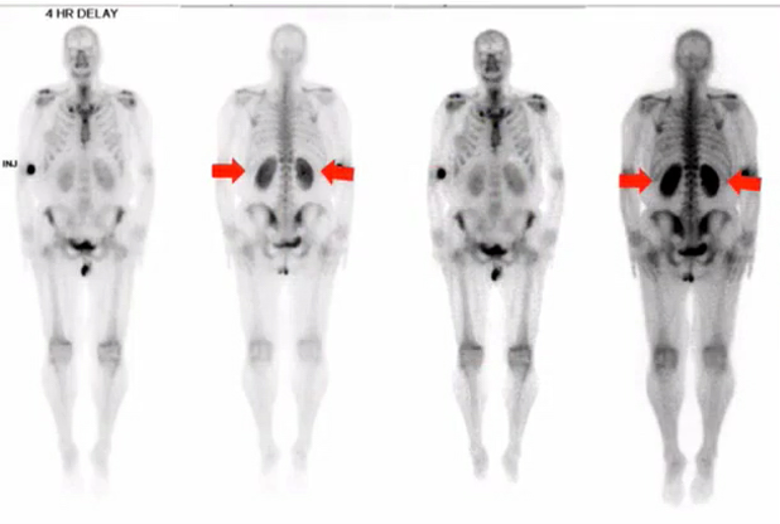

Two main causes of hot kidneys on MDP?